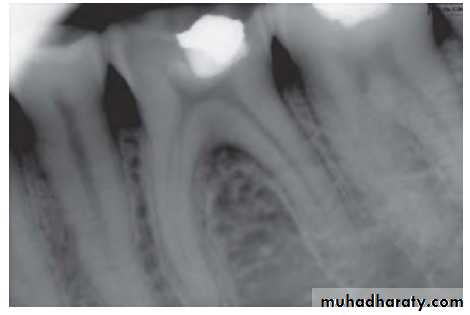

3. Radiographic changes:Radiograph shows a large cavity or restoration

4. Vitality test: Tooth is nonresponding to vitality tests. But multirooted teeth may show mixed response because only one canal may have necrotic tissue.

• Radiographic changes: small change to large periapical radiolucency

• Radiography helpful in determining the affected tooth as it shows a cavity or evidence of bone destruction at root apex.

• Radiographs show large area of radiolucency in the apex created by inflammatory connective tissue which has replaced the alveolar bone at the root apex